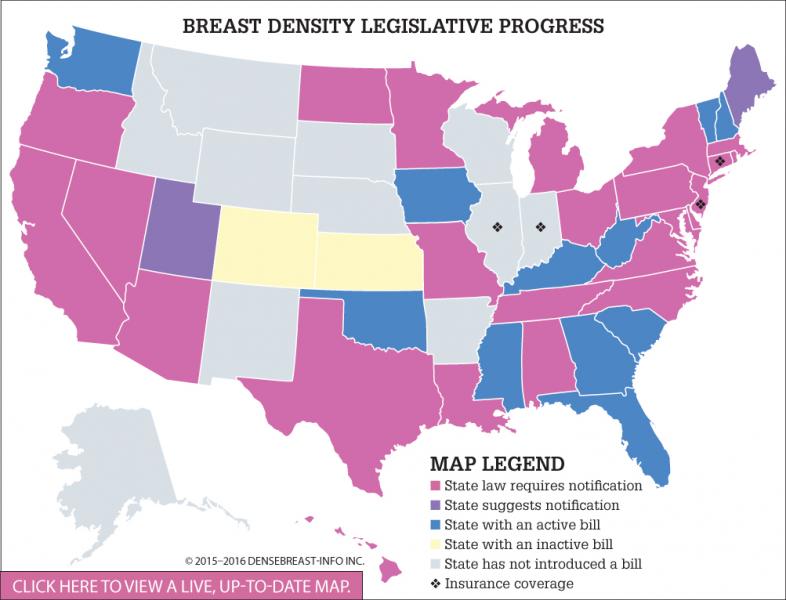

Breast density notification is an ongoing topic that gained a lot of momentum in 2015, and continues to do so in 2016.